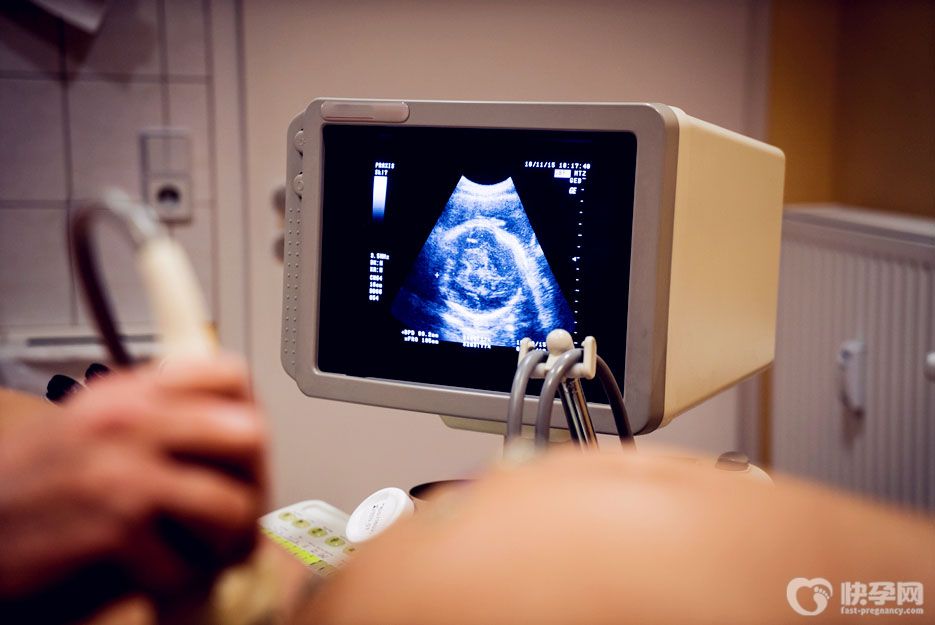

实际上,由于某些原因,一些胎儿的双顶径会更小。如果恰好是男宝,父母会认为双顶径会小生男孩。之后这种说法就在网上传开了,于是很多孕妇都认为是真的,并询问那些被验证过的人的经历。事实上,这种说法是不科学的。特别关注:网传双顶径偏小会生男孩是谣言-建议不信谣不传谣不造谣。

双顶径是医生用来观察判断孩子发育的数据,其数值与胎儿性别没有直接关系。如果双顶骨直径太小,不一定是生男孩,生女孩也有可能。建议孕妈妈不要轻信,胎儿双顶径太小是有害的,所以孕妈妈还是以孩子的健康为重。

每个孕妇的情况都不一样,所以胎儿的发育有个体差异,尤其是前三个月,胎儿发育较快时,其双顶径值大于那些发育较慢的宝宝,所以即使所有宝宝都怀的是男孩,宝宝的双顶径值也是不一样的。

Ps:需要注意的是,如果双顶径太小,说明胎儿可能有发育问题。孕妈妈要注意了。如果情况严重,胎儿可能发育不良,甚至出现智力低下。所以,女性在孕期一定要遵医嘱定期检查,保证营养均衡,适当运动,让自己保持良好的状态。

其实胎儿双顶径会随着月龄的增加而逐渐增大,这种变化会一直持续到分娩,每个宝宝的发育情况都不一样,所以很难说双顶径在生男孩以上多少。民间有一种说法,如果双冠直径在9.3cm以上,那么生男孩的概率就高,但有些女宝的双冠直径也在这个范围内。可见这种说法并不可信。建议各位准爸妈理性对待。